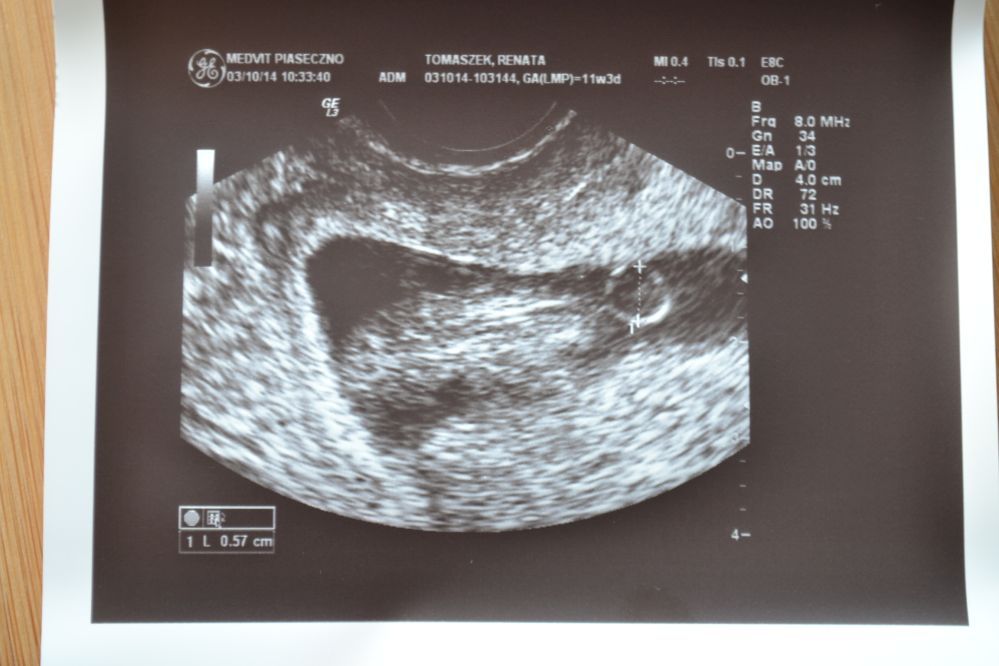

Jutro wkleję dwa zaległe zdjęcia i może trzecie świeże